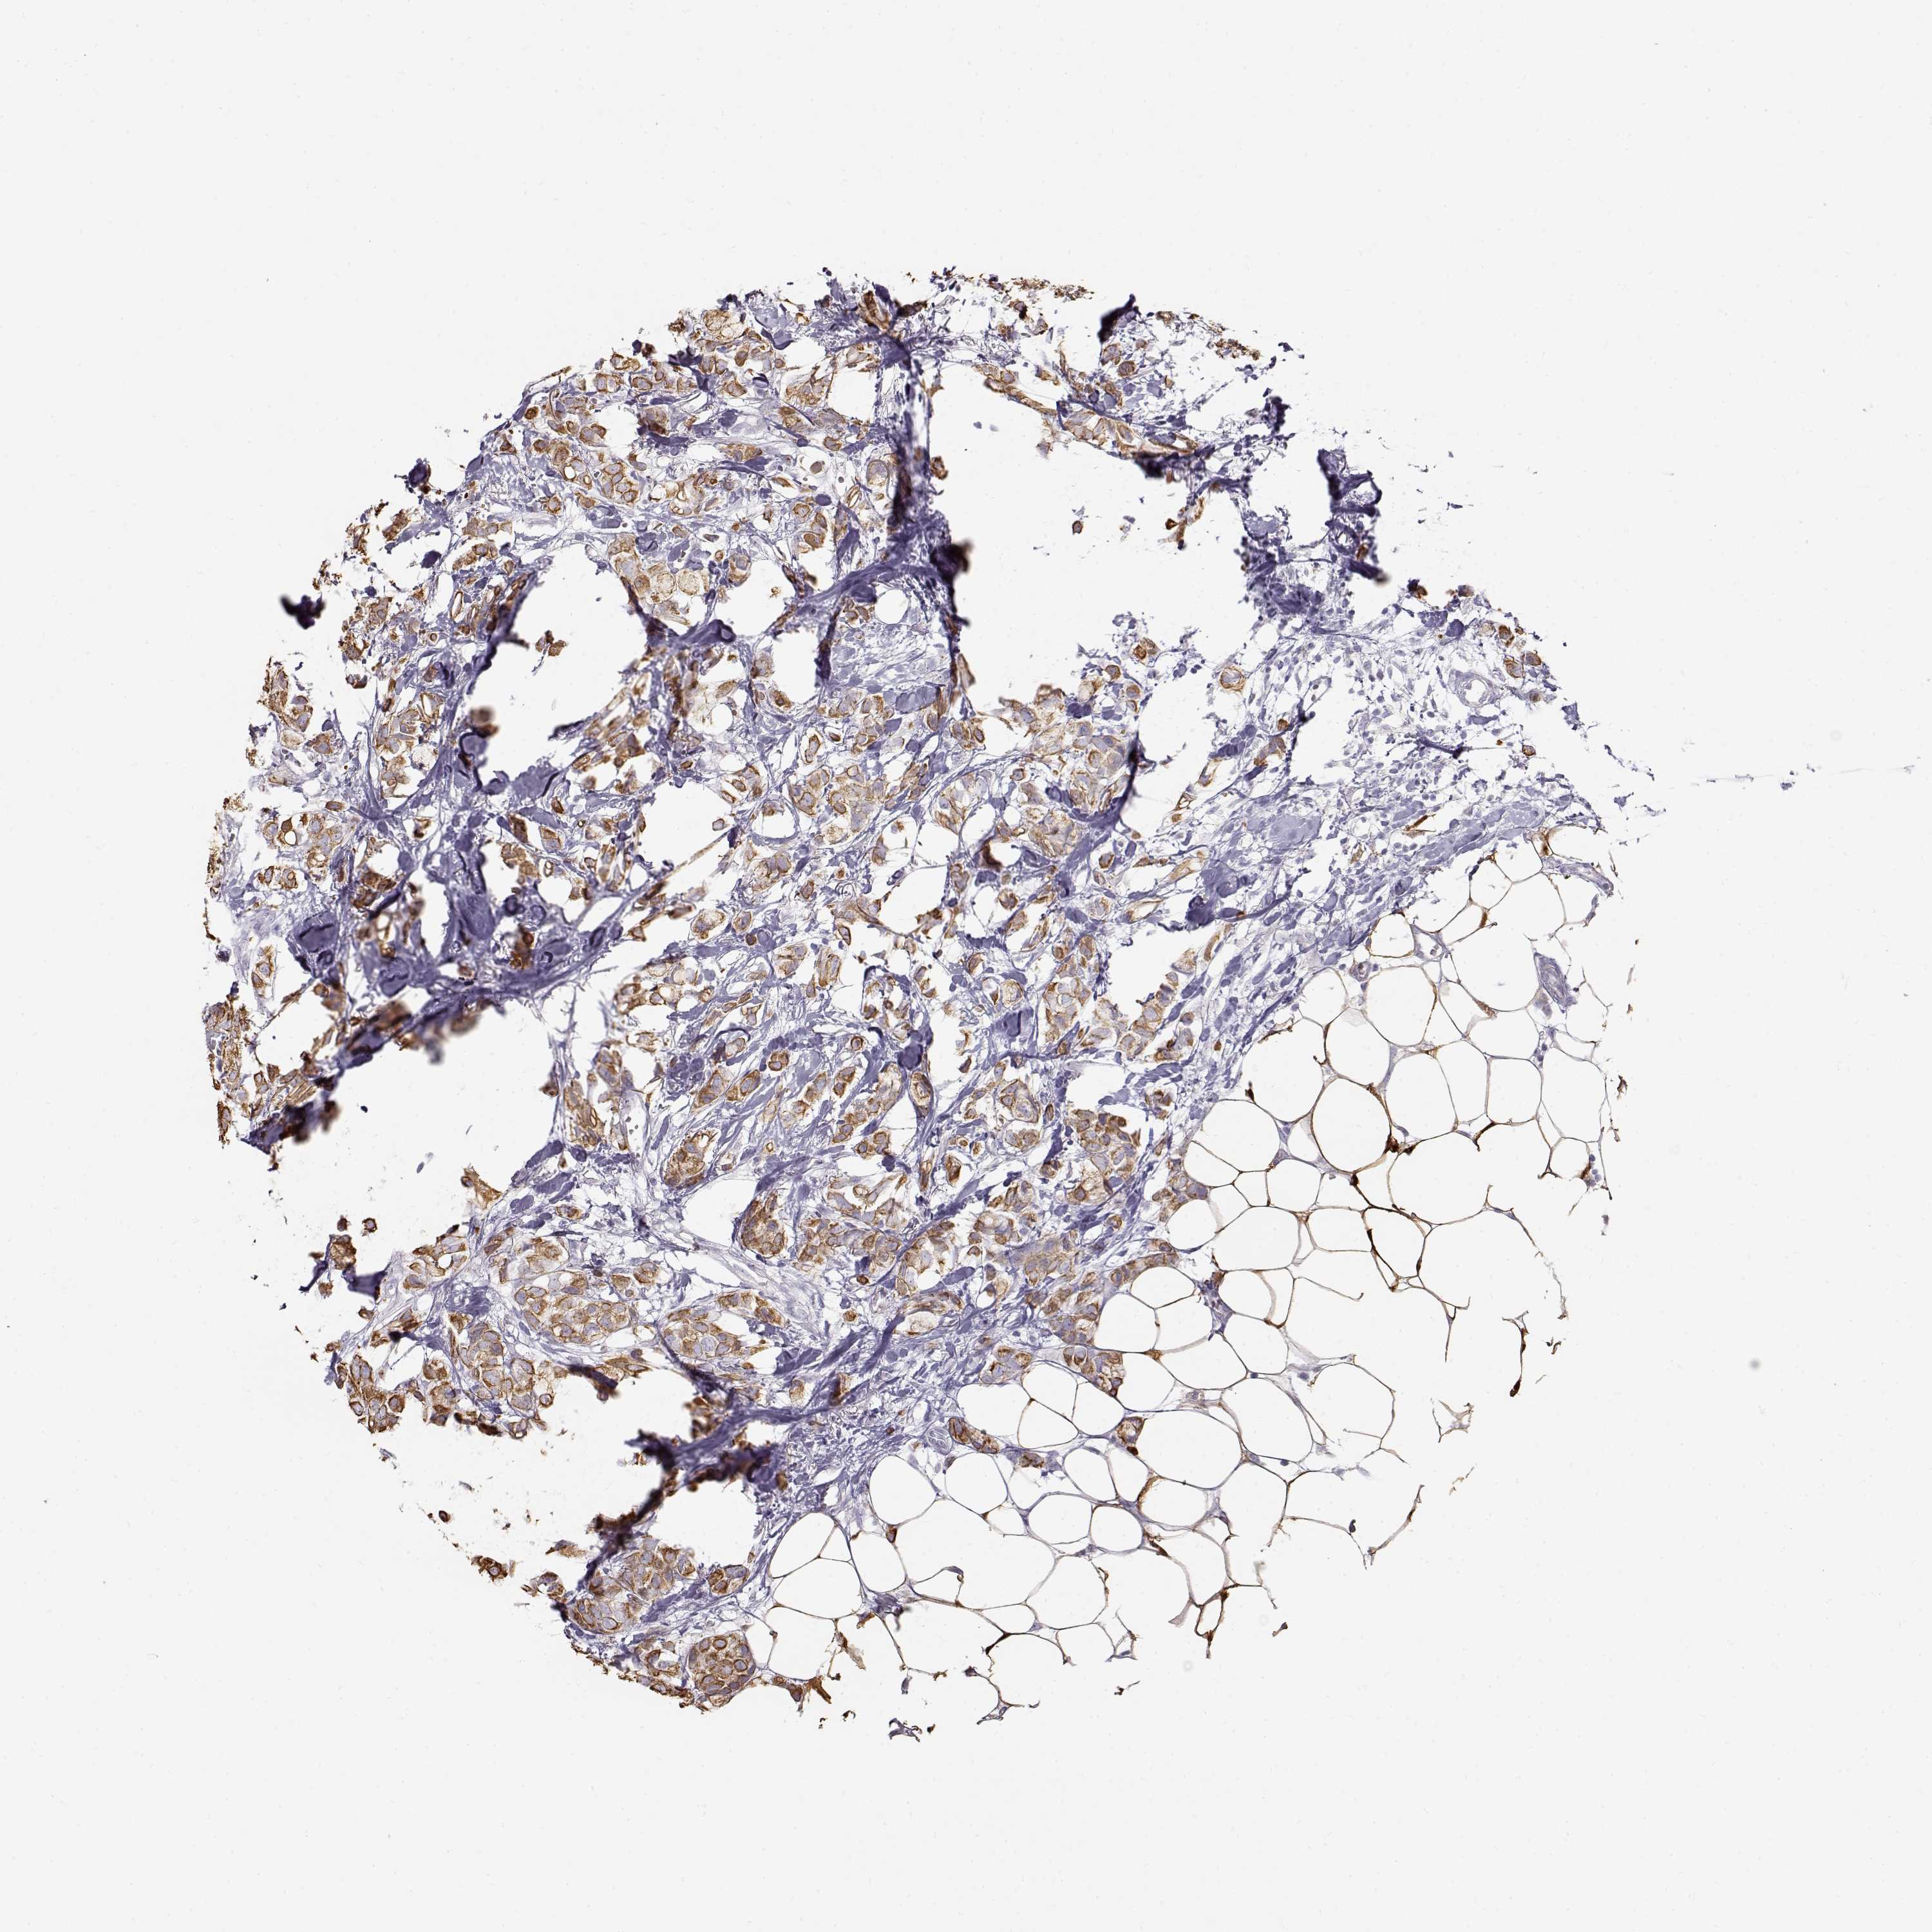

CANCER BREAST CANCER Show tissue menu

BRCA TCGA BRCA VALIDATION PROTEIN EXPRESSION